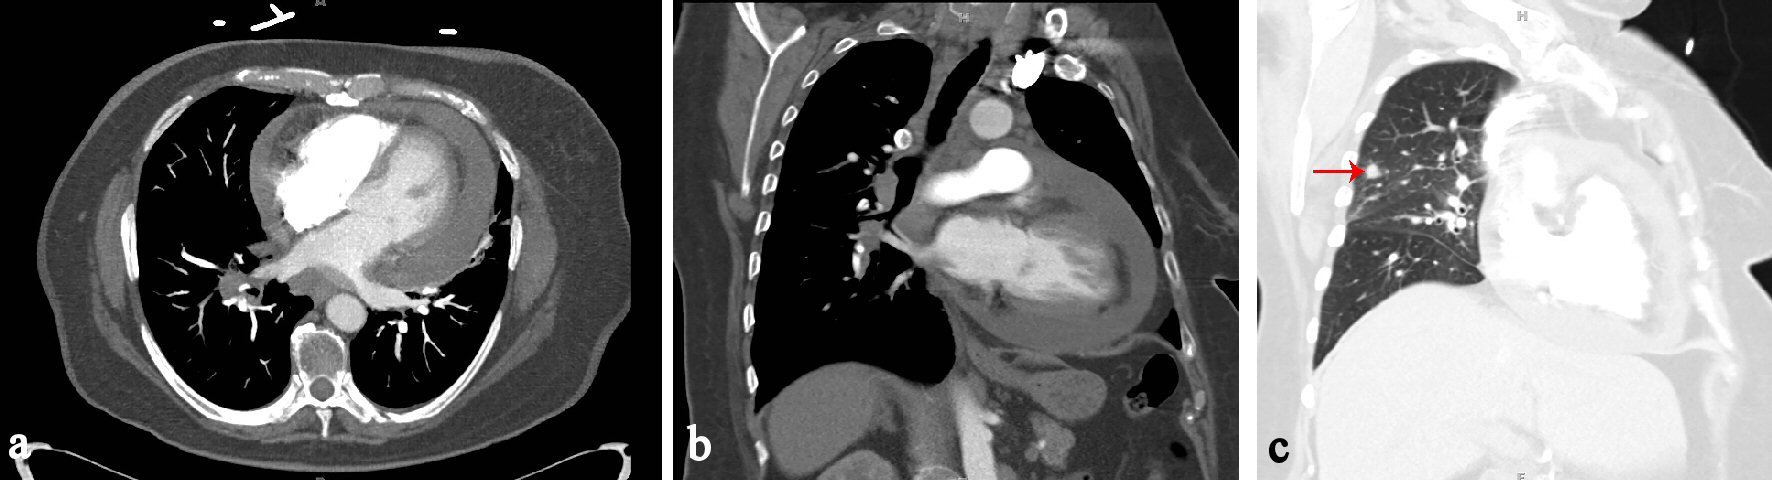

Figure 3. (a) CT chest axial view showing pericardial effusion. (b) CT chest coronal view showing pericardial effusion. (c) CT chest coronal view in lung window showing 7 mm nodule in right upper lobe (red arrow).